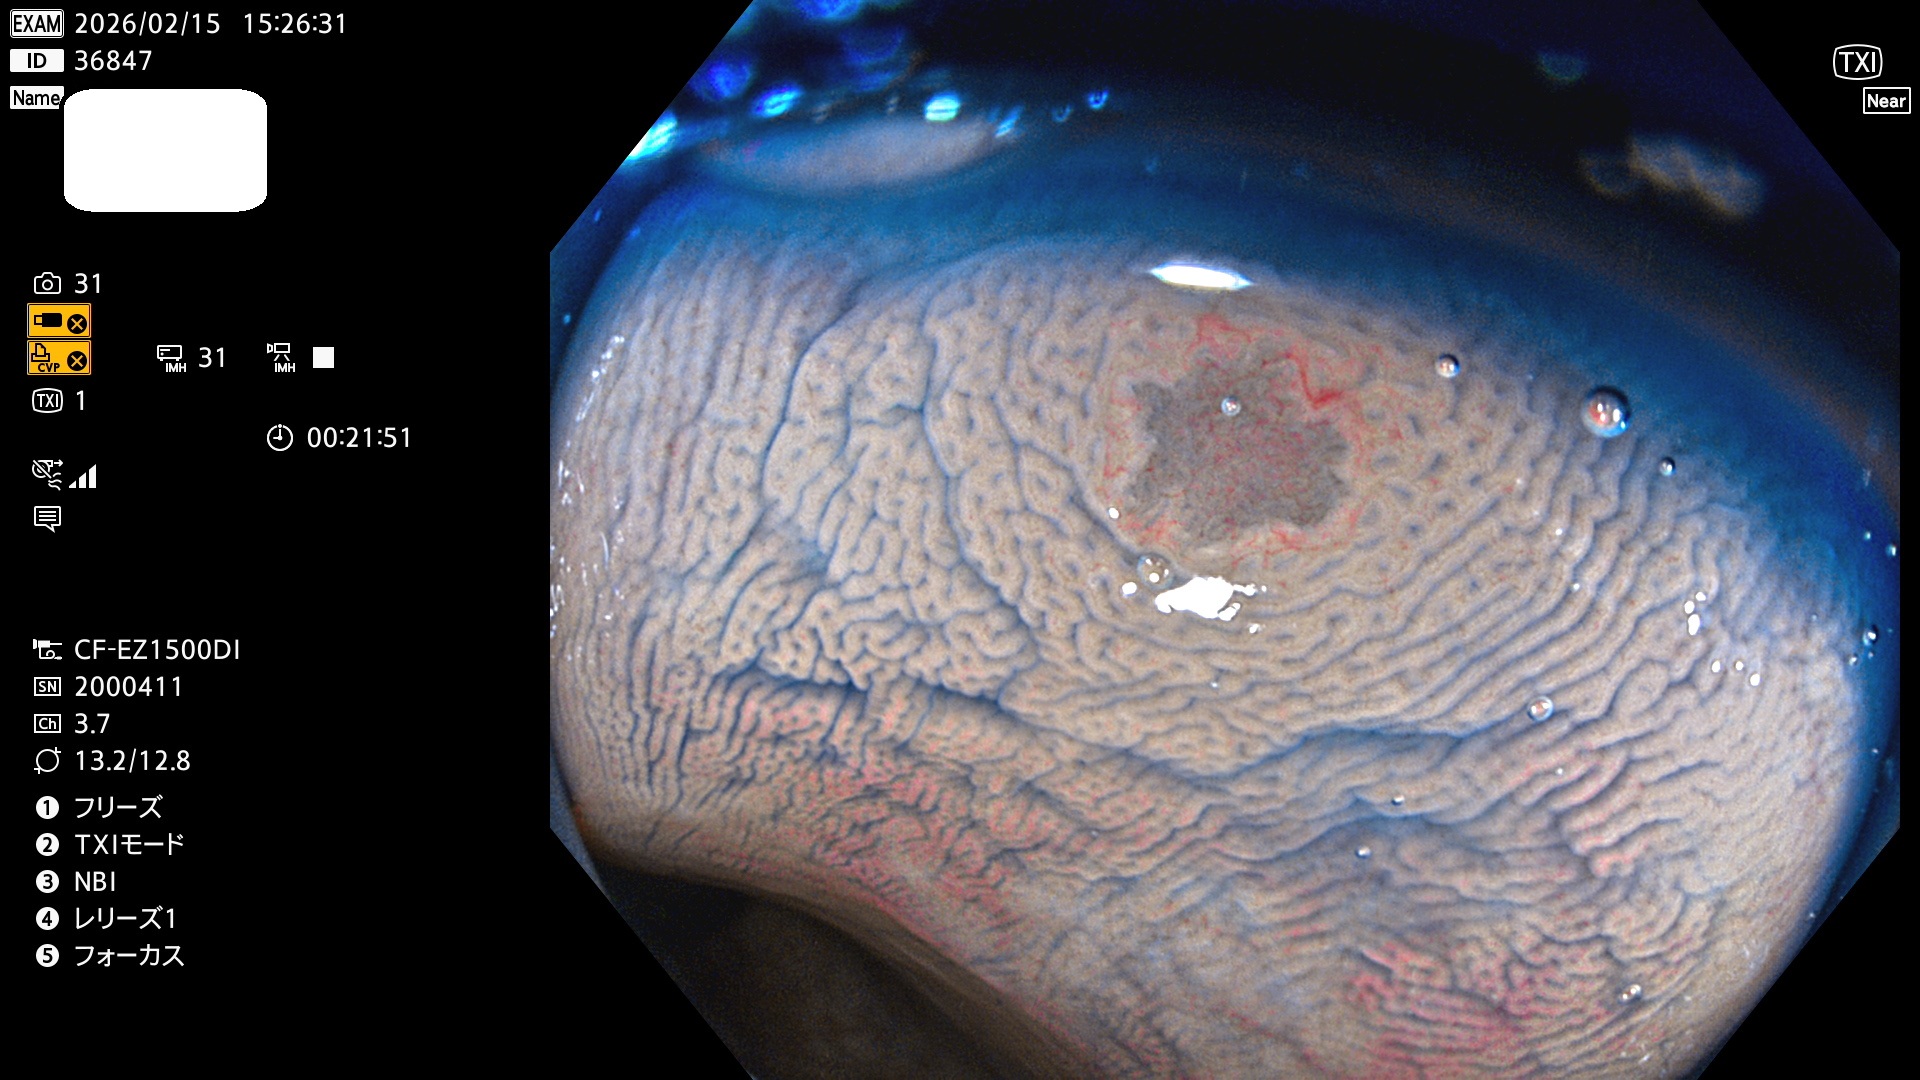

完全に平坦な物をUb、陥凹している物をUcと呼びます。Ubは認識が困難で、Ucはびらん(炎症)と紛らわしいために見落とされやすく、「内視鏡後・大腸癌」の原因になります。

毎週の検査(木・金・土・日)に発見されたUbとUc型・腺腫を、その週の日曜の夜にUPし1週間、提示します。

2026年2月12日〜2月15日の4日間(40件)5個 (Uc_ADR=5個/40人=13%)